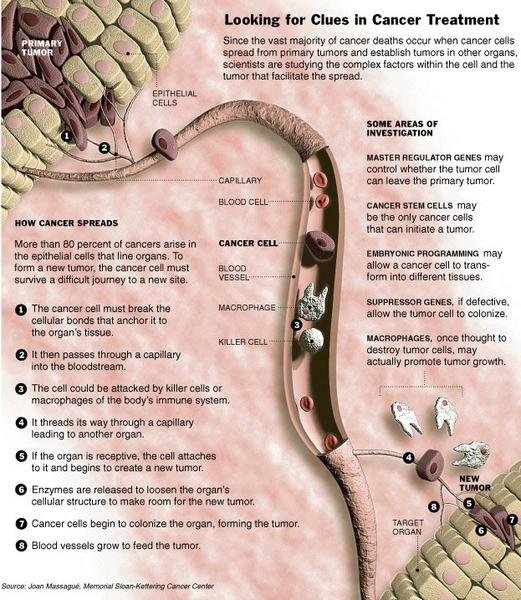

Scientists Begin to Grasp the Stealthy Spread of Cancer

The moment when a cancer begins to spread throughout the body — metastasis — has always been the most dreaded turning point of the disease. Without metastasis, cancer would barely be a blip on the collective consciousness. Fewer than 10 percent of cancer deaths are caused by the primary tumor; the rest stem from metastasis to vital sites like the lungs, the liver, the bones and the brain. Until the last five years or so, metastasis has remained something of a mystery.